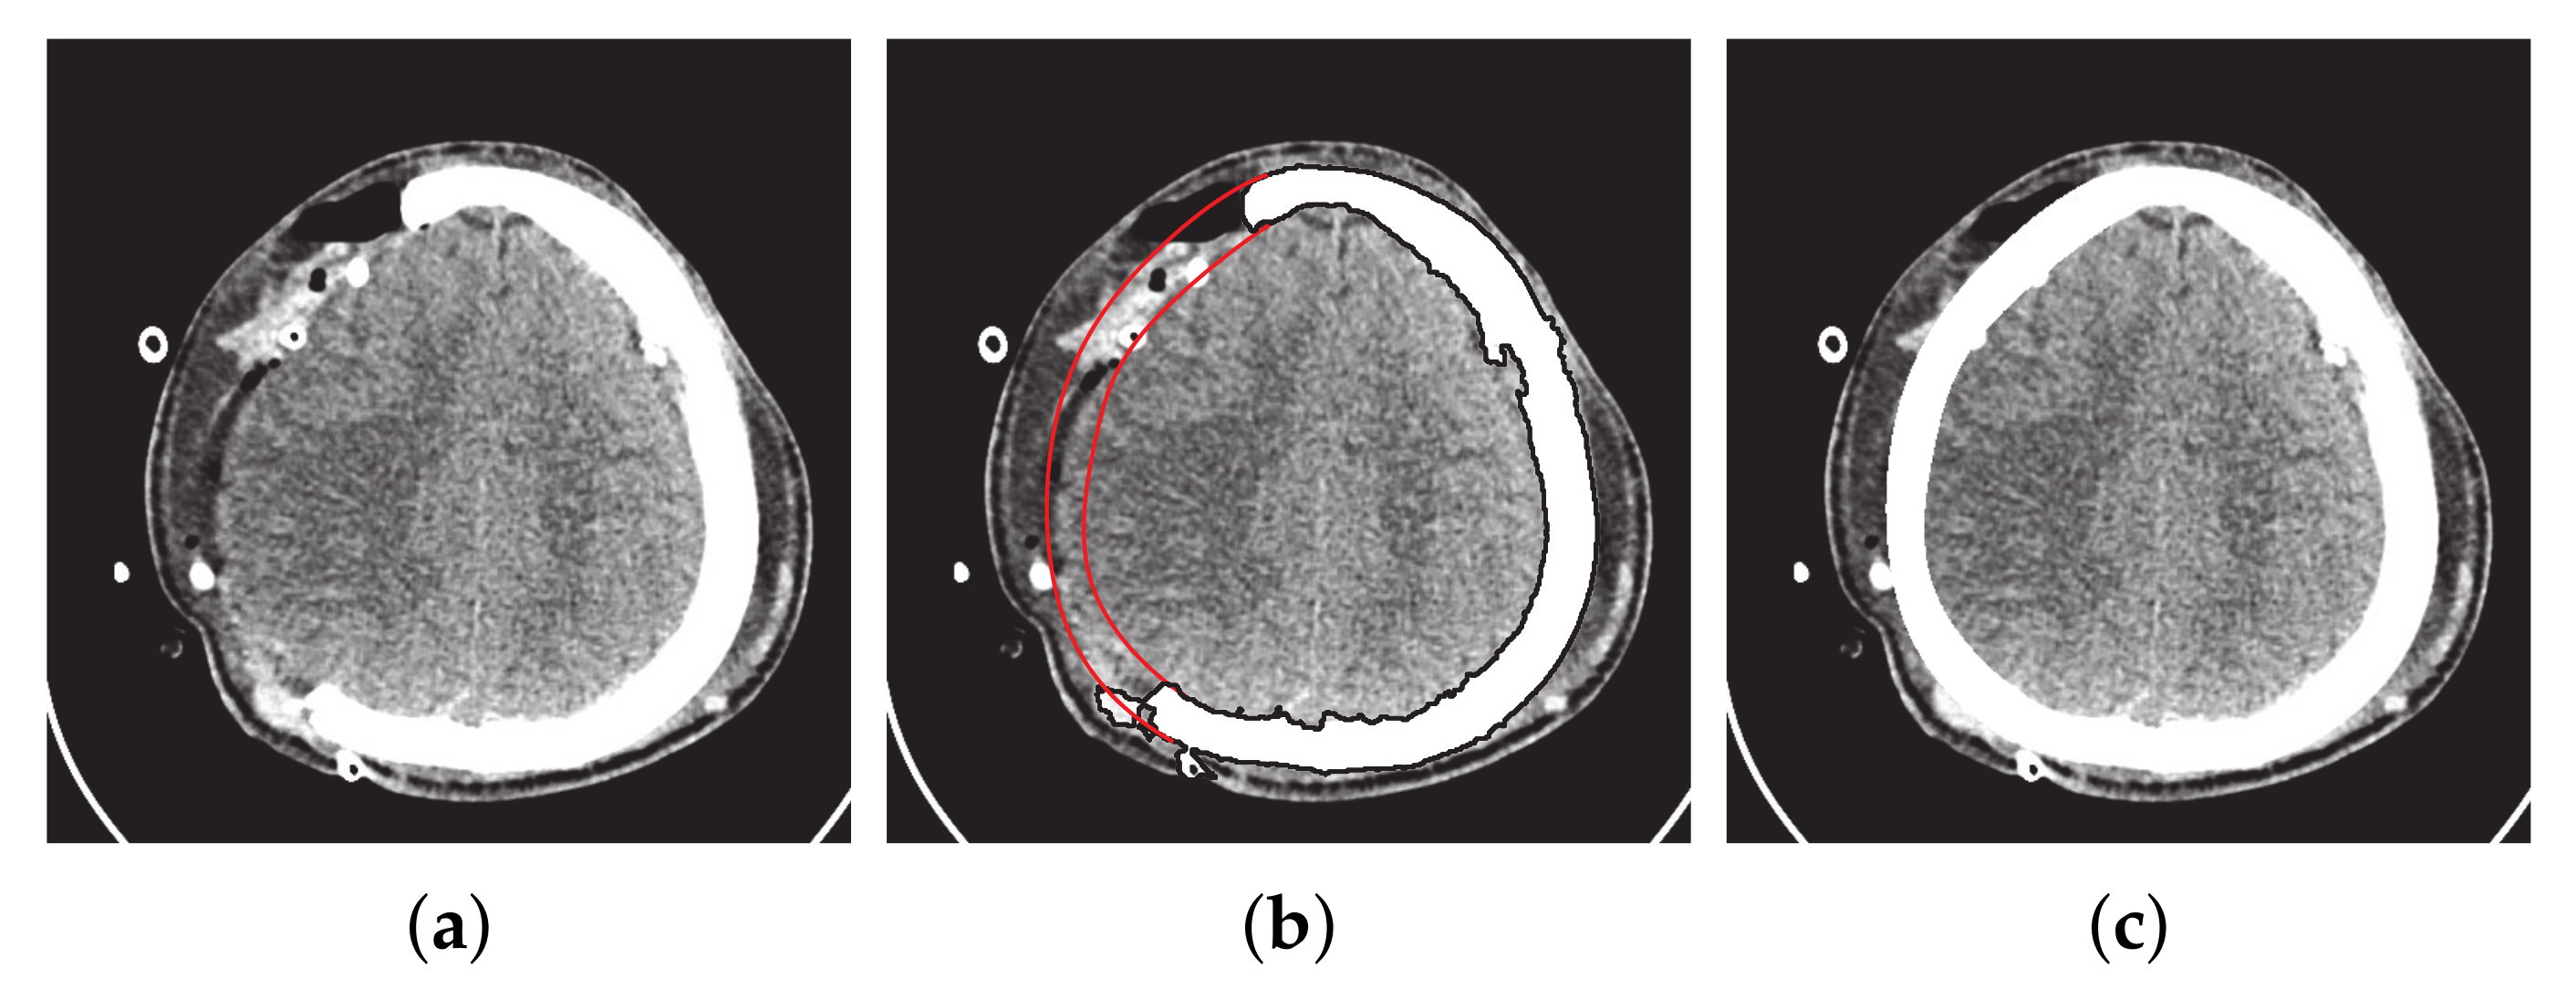

- Majeed, A.; Abbas, M.; Miura, K.T.; Kamran, M.; Nazir, T. Surface modeling from 2D contours with an application to craniofacial fracture construction. Mathematics 2020, 8, 1246. [Google Scholar] [CrossRef]

- Majeed, A.; Mt Piah, A.R.; Yahya, Z.R.; Abdullah, J.Y.; Rafique, M. Construction of occipital bone fracture using B-spline curves. Comput. Appl. Math. 2018, 37, 2877–2896. [Google Scholar] [CrossRef]

- Majeed, A.; Mt Piah, A.R.; Ridzuan, Y.Z. Surface Reconstruction from Parallel Curves with Application to Parietal Bone Fracture Reconstruction. PLoS ONE 2016, 11, e0149921. [Google Scholar] [CrossRef] [PubMed]